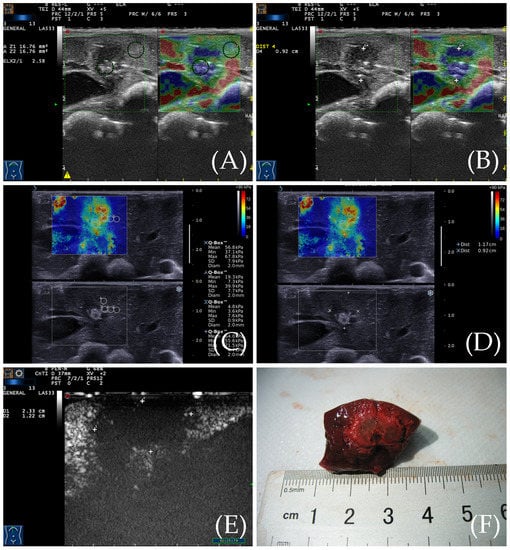

3.5. Gross Specimen Observation and Comparison of the Three Imaging Methods

Figure 3. (A) RTE elasticity image of the ablation zone. The even blue indicates the ablation zone, and its boundary is clear. The yellow, green, and red indicate the peripheral normal liver. (B) The diameter of the ablation zone was measured according to the elasticity image. (C) SWE elasticity image of the ablation zone. The ablation zone is indicated by three colors: yellow, green, and red. The peripheral normal liver is indicated by an even blue color. (D) The diameter of the ablation zone was measured according to the elasticity image. (E) After CEUS, the diameter of the ablation zone was measured by CEUS image. (F) The gross specimen of the ablation zone was measured after sacrifice.

Figure 4. The ablation area was measured by different measurement methods. There was no statistical difference in the area of the ablation lesions measured by RTE, SWE, and gross specimen. The area of ablation lesions measured by CEUS is larger than the first three, and their differences are statistically significant. Results are represented as the means ± SD. Blue dots mean RTE group, red dots mean SWE group, green dots mean Sample group, purple dots mean CEUS group, * p < 0.05.